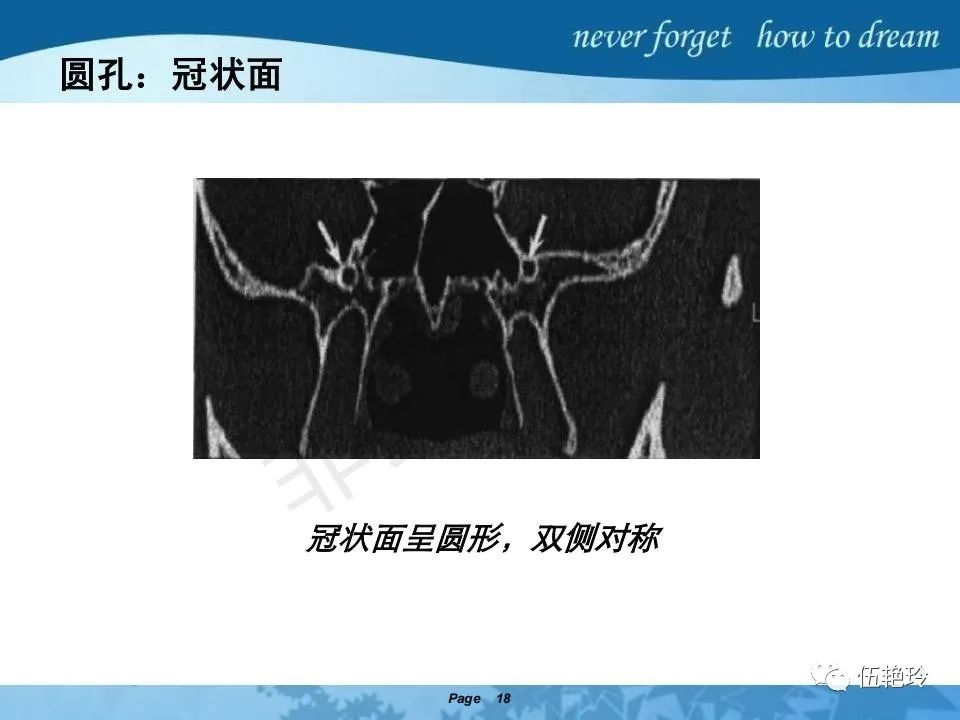

翼腭窝的解剖结构与鼻咽癌侵犯

2.2 鼻咽特有的解剖途径:鼻咽癌原发灶循序进展的总途径:鼻腔(47.8%)→翼腭窝(15.2%)→ 眶下裂(3.2%)→眶尖(1.2%)→海绵窦(0.6%)。

2.31 向上颅内:①鼻咽顶壁→破裂孔(岩尖、斜坡)→蝶窦、海绵窦;②鼻咽顶壁→蝶骨基底部→蝶窦、海绵窦;③鼻咽侧壁→茎突前间隙→蝶骨大翼(卵圆孔)→海绵窦;④鼻咽侧壁→茎突前间隙→翼腭窝→ 颞下窝;⑤鼻咽前壁→鼻腔→翼突、翼腭窝→眶下裂→眶尖→海绵窦;⑥鼻咽前壁→鼻腔→上颌窦、筛窦;